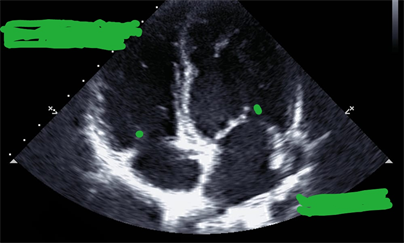

Vascular echocardiography reveals gangrene of the leg up to 5cm from the knee and mild aortic stenosis (see Figure 2).

Figure 2. Cardiac ultrasound section showing aortic stenosis.